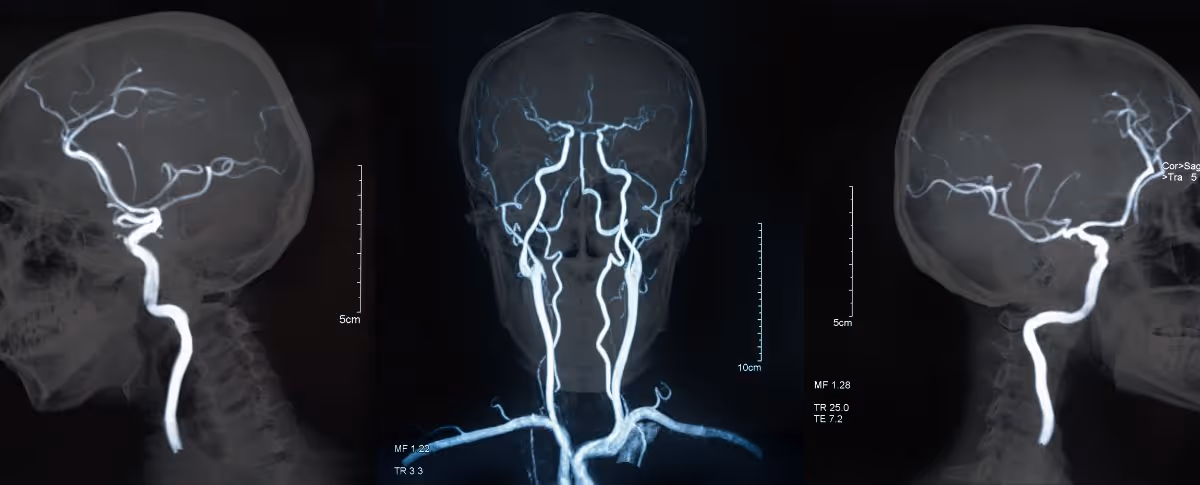

MRA is a non-invasive imaging technique to detect abnormalities in blood vessels and the circulatory system. This advanced method is especially useful in diagnosing vascular diseases such as atherosclerosis.

MRA is a non-invasive imaging technique to detect abnormalities in blood vessels and the circulatory system. This advanced method is especially useful in diagnosing vascular diseases such as atherosclerosis or thrombosis. Doctors may use contrast agents to enhance image clarity and diagnostic accuracy in certain patients.

MRA harnesses magnetic and radio waves to produce detailed 2D or 3D images of blood vessels and the circulatory system. This technique can identify vascular abnormalities such as stenosis or blockages.

MRA is a specialized MRI technique specifically focused on evaluating the blood vessels and the circulatory system. MRA is particularly effective in diagnosing vascular conditions such as arterial stenosis, aneurysms, or tumors in blood vessels.

An MRA provides detailed images of the blood vessels in the body, allowing doctors to detect abnormalities, diagnose conditions, and plan appropriate treatments. It helps monitor the progress of vascular treatments and assess the risk of stroke and heart disease.